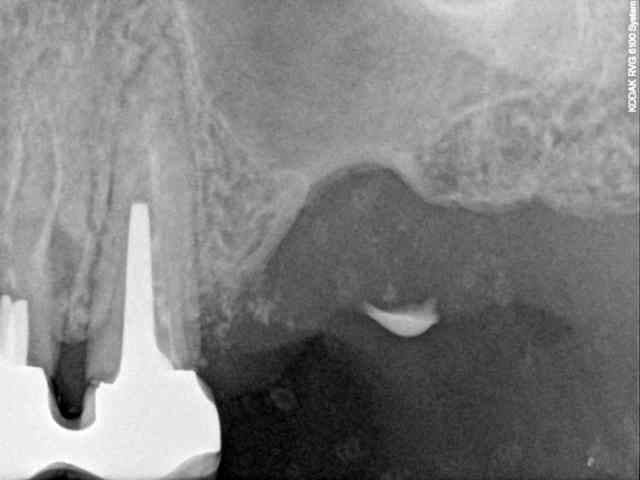

je dois pratiquer un rehaussement de plancher sinusien par volet latéral et je ne sais comment gérer le décollement de la membrane de Schneider au niveau de la communication bucco sinusale

Dès le départ, je m'inquiète au niveau du décollement du lambeau sur la CBS, on risque de déchirer à ce moment là

je joins quelques captures pour vous faire une idée

je ne vois pas de septum dans la zone de comblement

pourrais-tu préciser?